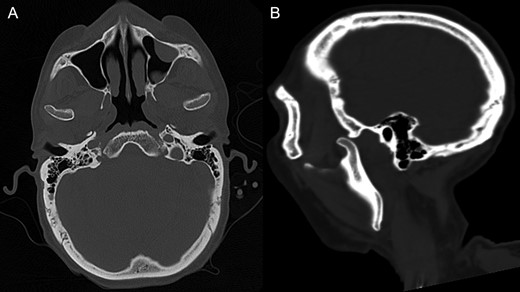

On the fifth day after a lung transplant, in the intensive therapy unit, the patient begins to experience symptoms of mandibular pain, trismus and extrapyramidalism symptoms in the form of oromandibular dystonia. In physical exam he presented signs of bilateral jaw subluxation with reuptake inhibition of the articular condyle–disc complex, contraction at the masticatory muscles level, fascies dolorosa, dystonia of the facial third with articular blocking and incapacity for bucal closure or lateral excursion and slight dysphagia. As background of the hospitalization, he had received, an hour before said event, 2.5 mg of haloperidol and 0.25 mg of risperidone (two doses) due to hyperactive delirium. It was decided to take a computed tomography (CT) of the craniofacial complex and brain without IV contrast (Fig. 1), where the following was seen: dislocation of both mandibular condyles with anterior position to the temporal’s glenoid cavity, without evidence of associated bone injuries.

CT of the craniofacial skeleton without contrast showing the bilateral dislocation of mandibular condyles. (A) Shows as axial section and (B) sagittal section.